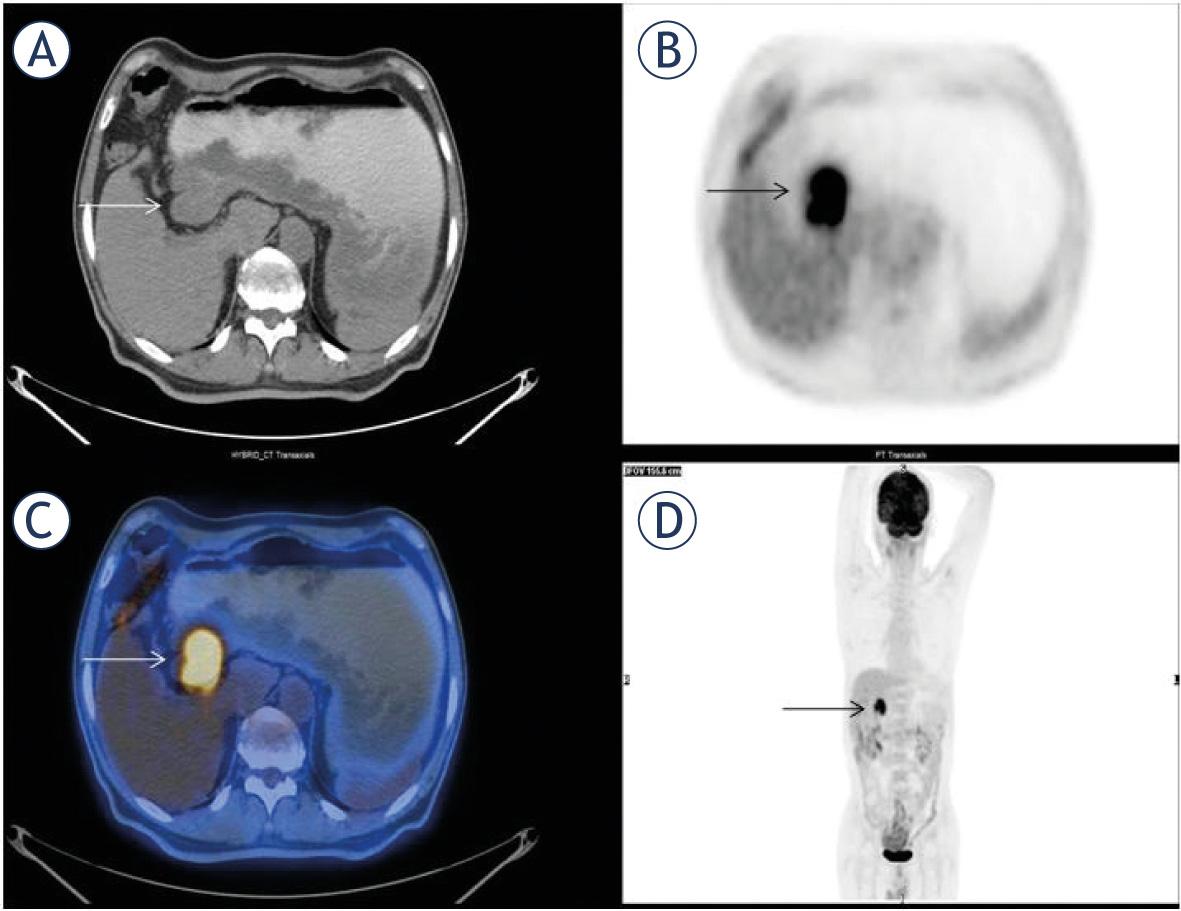

The most frequent form of PEL is constituted by GIS lymphomas. Stomach is the most common site of primary GIS lymphoma and MALT lymphoma is the most common variety.10 Small intestine fills the second ranking. A heterogeneous group of lymphomas including MALT, DLBC, MC, Burkitt and T cell affect the small bowel. Primary colon lymphoma has features similar to small bowel disease with wall thickening without obstruction.11 DLBC, Burkitt and T cell lymphomas are strongly FDG-avid. 25/67 (37%) of our patients had primary GIS lymphoma. 14/25 (56%) of them were primary gastric lymphoma, 5/25 (20%) primary intestinal lymphoma and 5/25 (20%) primary colon lymphoma. 5/14 (36%) of gastric lymphomas were MALT type, while 8/14 (57%) DLBC variant (Figure 3). DLBC variants exhibited usually high FDG accumulation. MALT types had variable (usually moderate) up-take. Our incidence of gastric DLBC outnumbered gastric MALToma. This is an interesting result contrary to the literature. Other findings are nearly the same as in previous studies.

There was a mass in antrum of stomach on transaxial CT (A), PET (B), fusion (C) and MIP images (D) (arrows) of a 60-year old female patient with primary gastric lymphoma of DLBC type. She had metabolic tumor parameters of SUVmax: 11, SUVmean: 5, MTV:34 cm3, TLG:150. Her outcome was excellent with a DFS and OS of 111 months.